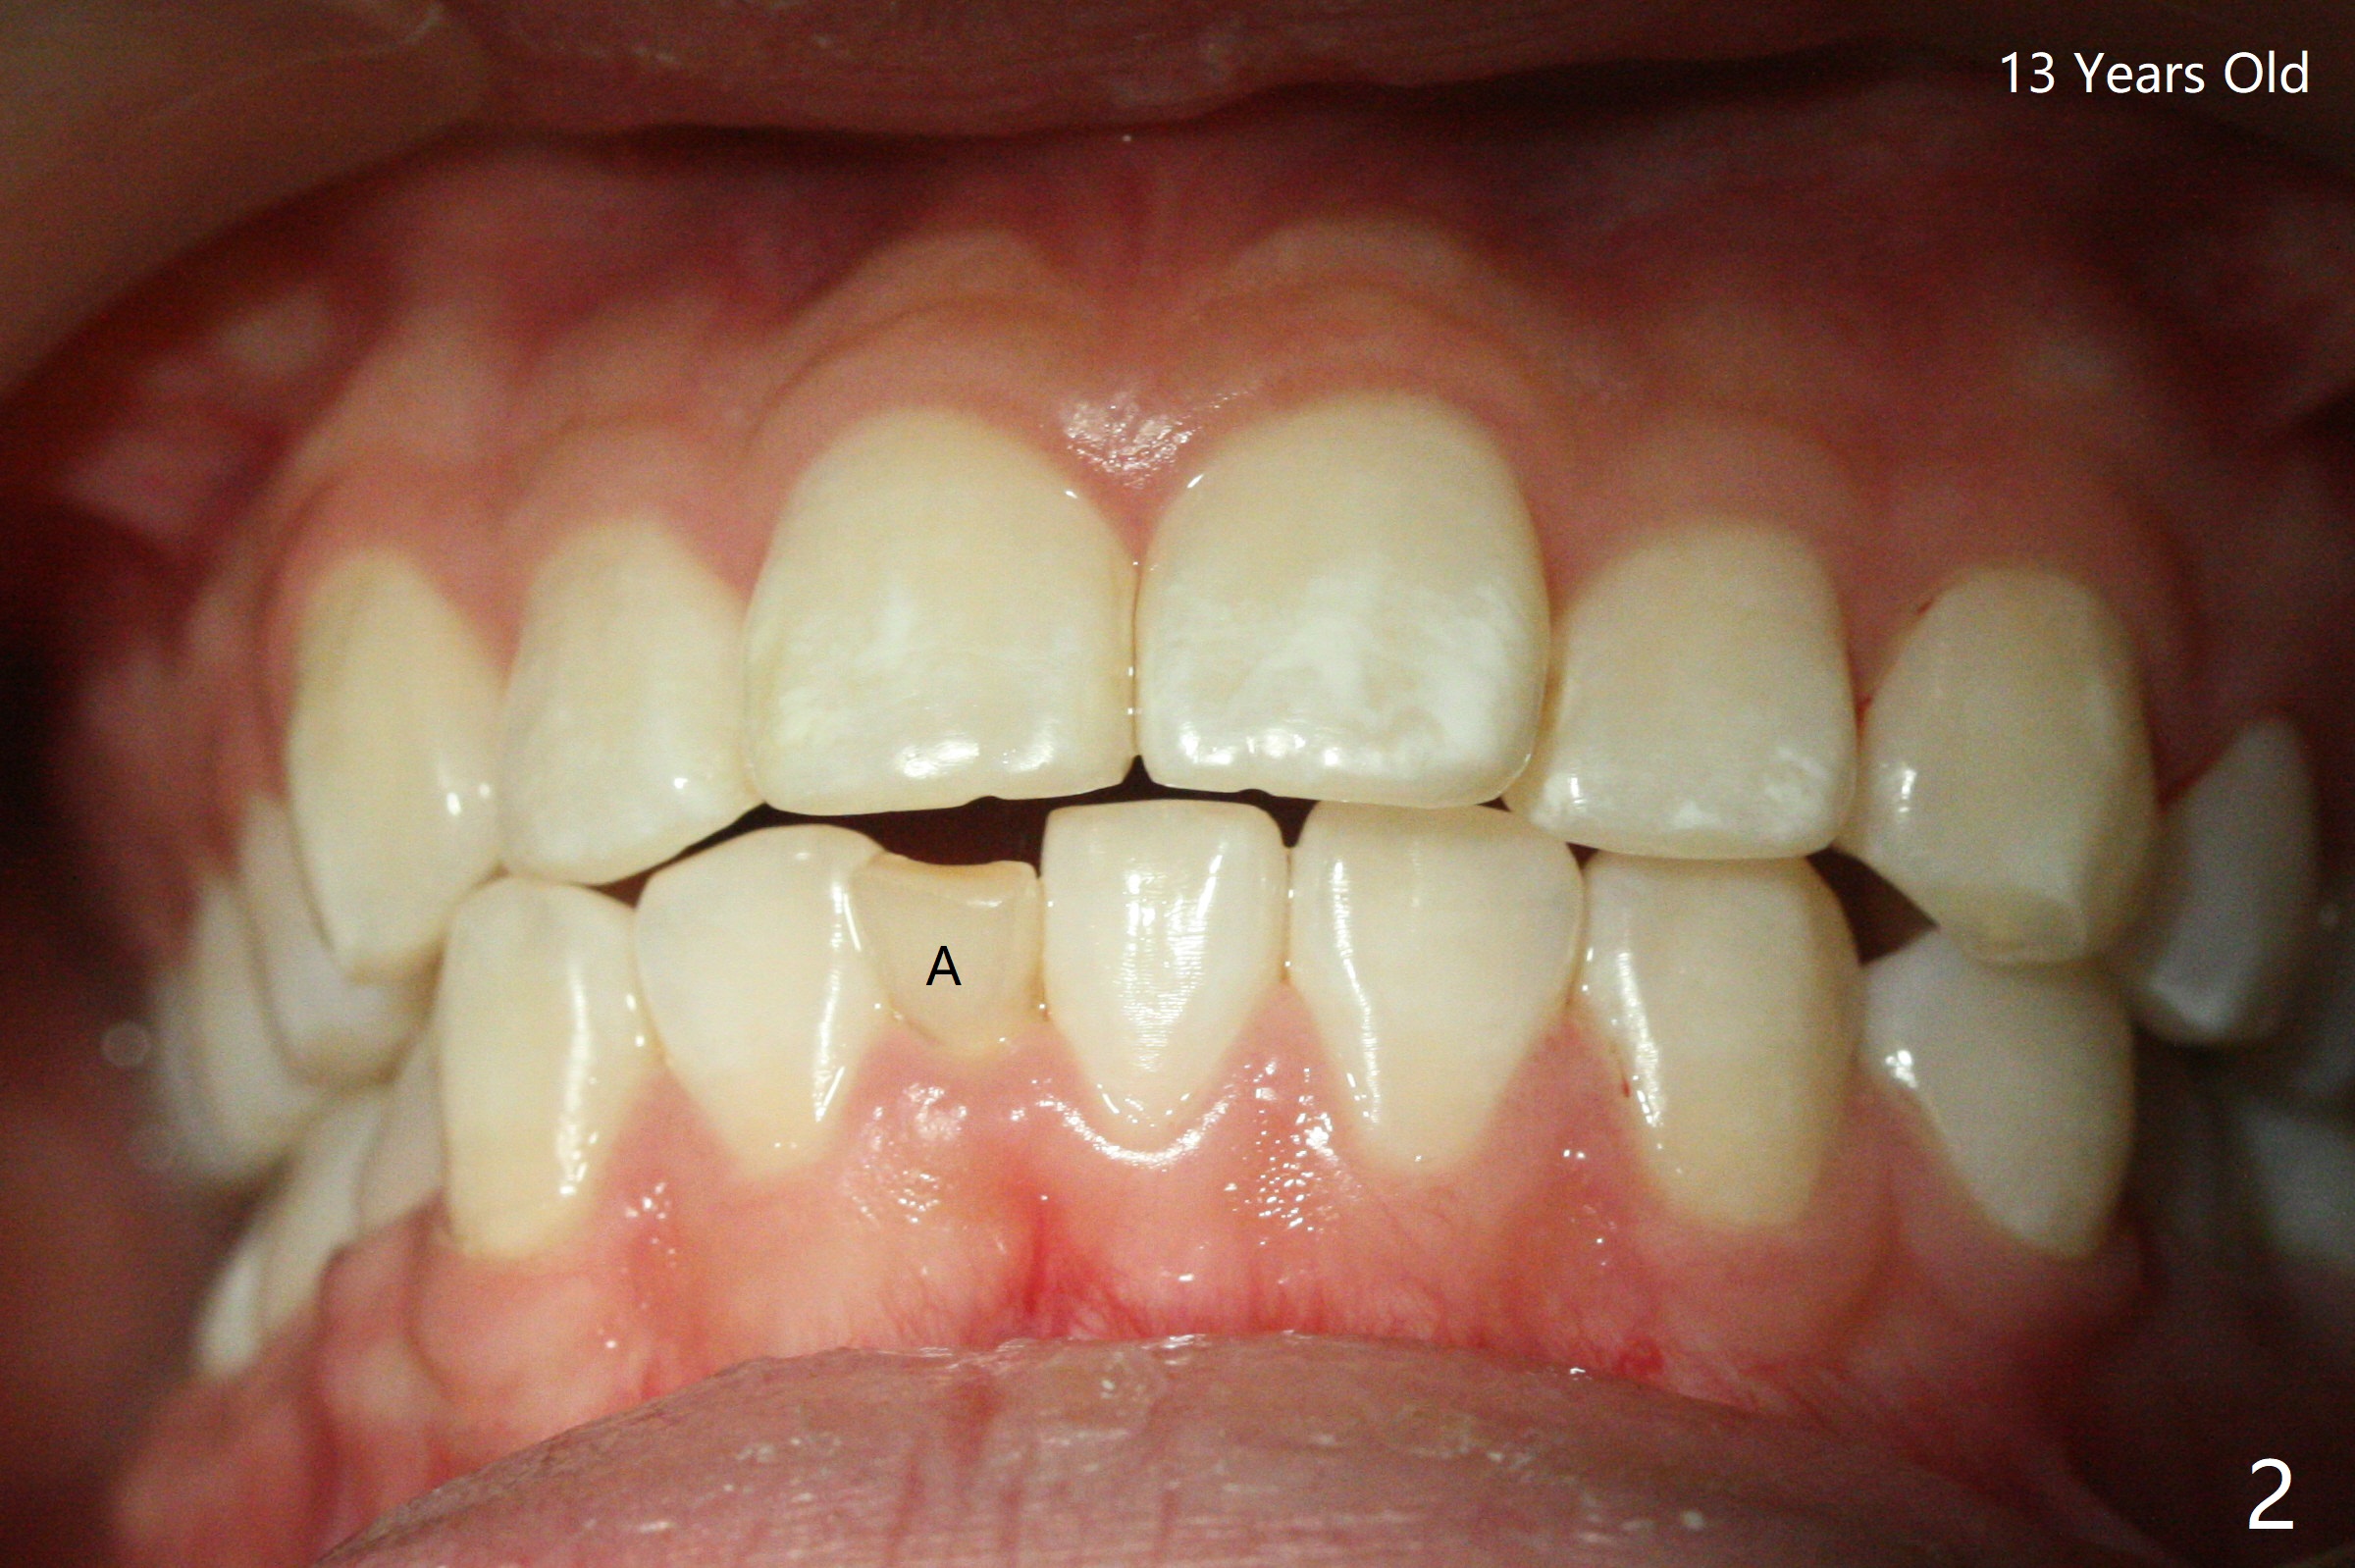

A 7-year-old woman has congenital missing lower right central incisor (Fig.1). At age of 13, she requests extraction of the displaced and discolored deciduous central incisor (Fig.2,3 A). After extraction, self drifting may alleviate crowding and anterior overjet and closes the space? Perfect solution, extract the A followed by driftodontics...fixed appliances as needed. Dr. Shaughness 12/25/2019